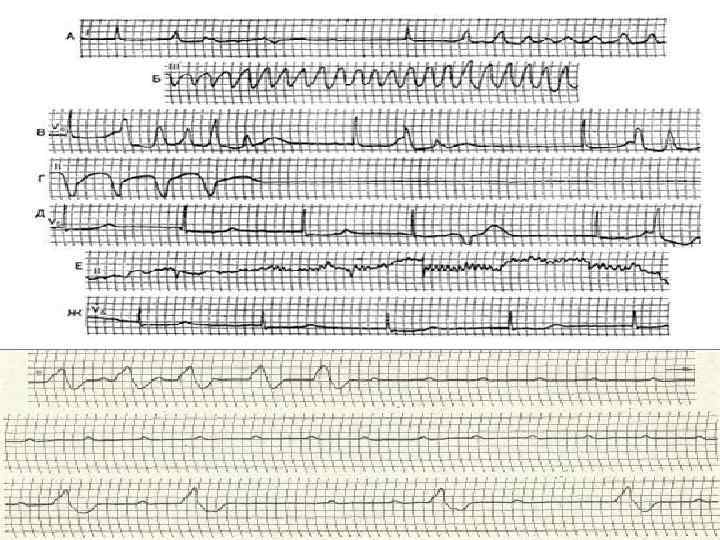

ИНСТРУМЕНТАЛЬНЫЕ МЕТОДЫ ДИАГНОСТИКИ. • ЭКГ: 1. Дисфункция САУ – СБ, остановки САУ, СА блокада. Отсутствие дыхательной аритмии. 2. Замедление вп проводимости. 3. Нарушения АВ проводимости. 4. Снижение амплитуды комплекса QRS. 5. Замедление вж проводимости и процессов реполяризации желудочков - увеличение продолжительности QRS и QT. 6. Признаки коронарной недостаточности – уплощение и инверсия зубцов Т, депрессия или элевация сегмента ST.